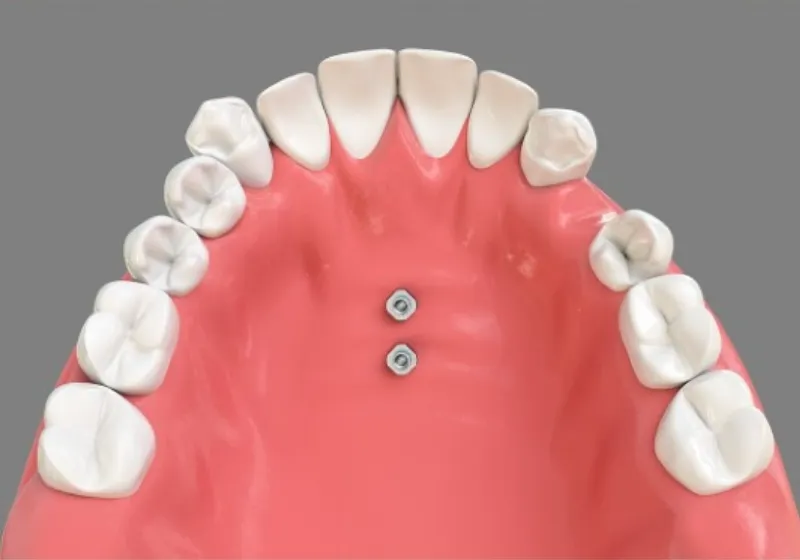

MSE(上顎骨骨格性拡大装置)は、矯正用アンカースクリューを使って上顎の骨を横に拡大する装置です。上顎の骨は左右に分かれており、その真ん中に正中口蓋縫合とよばれる骨のつなぎ目があります。MSEは、この骨のつなぎ目の右と左にそれぞれ2本ずつ、計4本のアンカースクリューを埋め込んで固定します。これによって左右の骨が少しずつ引き離され、その間に新しい骨が形成されることで、上顎の骨を横へと拡大できます。

体への負担を軽減できる

10代前半までは顎の成長を促進して骨格的に拡大することができますが、高校生以上や成人の場合はそのような治療ができないため、以前は全身麻酔で上顎の骨を切って広げる外科手術が必要でした。しかし、MSEを使えば、局所麻酔でアンカースクリューを埋め込むだけで上顎の骨を簡単に拡げることができます。子どもから40~50代の矯正治療にも効果的で、骨を切る外科手術に比べて患者さまの負担が大幅に軽減することが可能です。